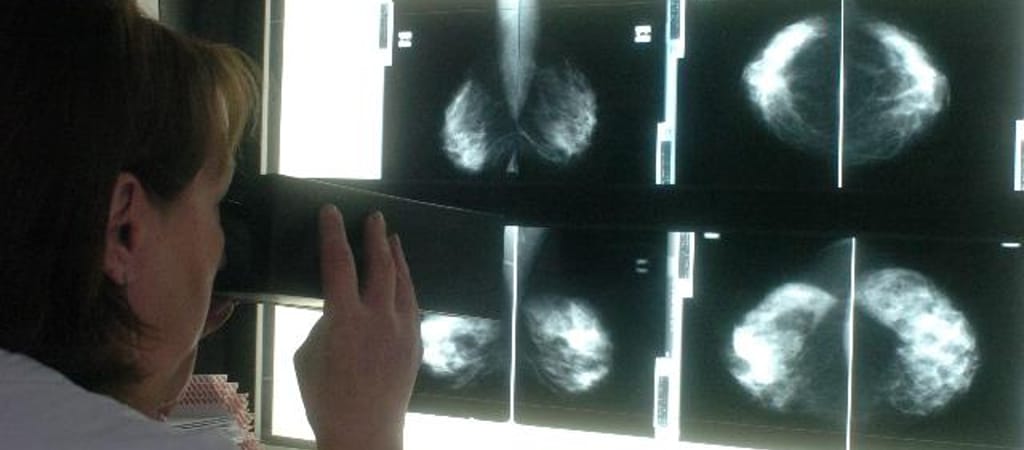

Első körben a háziorvoshoz kell fordulni, aki szükség esetén további vizsgálatokra küldi a beteget. A diagnózis felállítása esetükben is mammográfiával, emlő UV vizsgálattal és core-biopsziával, azaz úgynevezett vastagtű segítségével vett szöveti mintavétellel történik, ám náluk gyakran már más szerveken is áttétek vannak, amikor kiderül, hogy baj van.